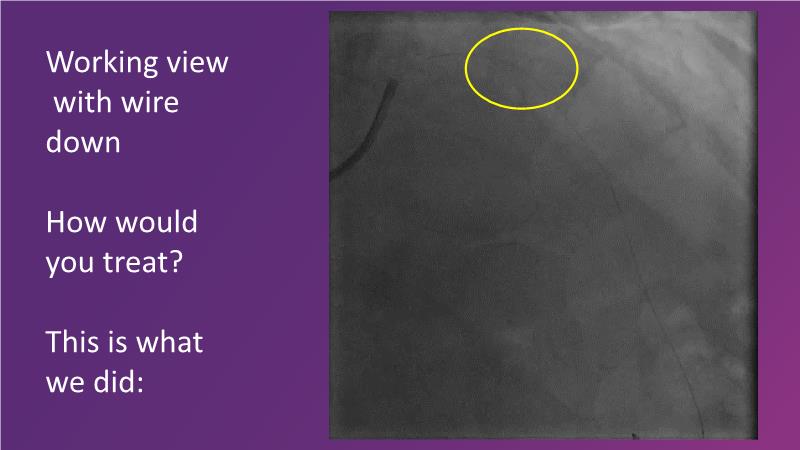

- To learn about the importance of vessel preparation and which tool to use when

- To review clinical scenarios when a stent is not required